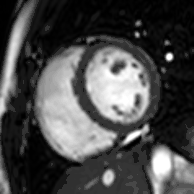

Enlarged right ventricle with poor function in a patient with repaired tetralogy of Fallot by CMR